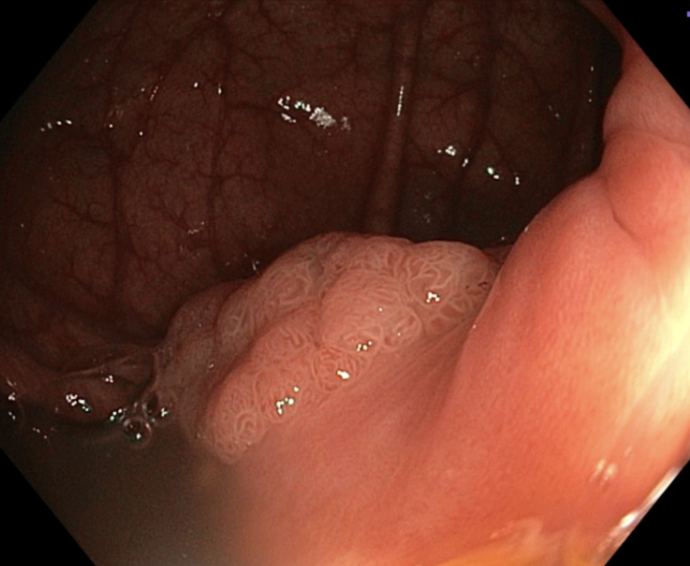

Sõna polüüp võib esmapilgul kõlada hirmutavalt, kuid meditsiinis tähistab see healoomulist moodustist. Samas võib polüüp ebasoodsate asjaolude kokkulangemisel aja jooksul areneda pahaloomuliseks kasvajaks. Mõistet „polüüp" kasutatakse meditsiinis mitmes erinevas kontekstis, kuid seedetraktis tähendab see enamasti väikest moodustist sooleseinal.

Polüübid on ebanormaalsete rakkude kogumikud, mis tekivad soole limaskestas. Enamik neist on õnneks healoomulised, kuid mõned polüübid võivad aja jooksul muutuda pahaloomuliseks. Enamus jämesoolevähkidest saab alguse esialgu healoomulistest polüüpidest, mis aja jooksul arenevad vähkkasvajaks. Seetõttu on oluline jämesoolepolüüpide varajane avastamine ja eemaldamine.

Koloskoopia on siinkohal parim abimees, võimaldades näha jämesoolt kogu ulatuses ja eemaldada polüübid tavaliselt juba esimesel protseduuril. Oluline on kaasaegse tehnoloogia kasutamine – AI võimekusega koloskoopia tõstab väikeste polüüpide leidmise tõenäosust võrreldes tavalise koloskoopiaga.